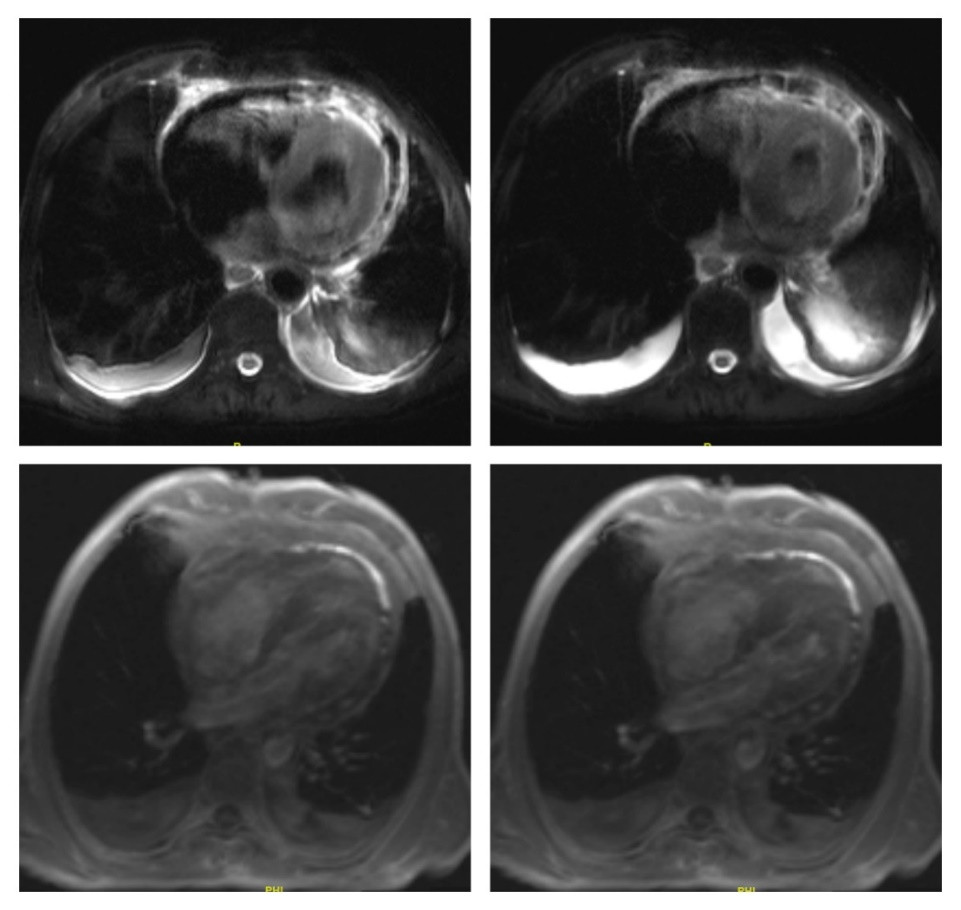

| 图 2 心脏磁共振检查图像 |

急诊医师结合患者疼痛症状、心肌标志损伤物升高及心电图广泛ST段抬高,误诊为急性心肌梗死,给予抗血小板、抗凝、抗心肌缺血等对症治疗后症状未见明显缓解, 遂行急诊冠脉造影术,见主支血管通畅未见狭窄,收入院治疗。查体:体温36.3℃,血压101/84 mmHg(1 mmHg=0.133 kPa),心率84次/min,双手掌指关节、近端指间关节肿胀伴压痛,余未见明显异常。患者入院第二天检验情况:血沉104 mm/h;超敏肌钙蛋白T 0.415 ng/mL;肌酸激酶93 U/L、肌酸激酶同工酶10 U/L;C-反应蛋白175.2 mg/L;白介素-6 221.27 pg/mL;类风湿全项:抗波形蛋白抗体MCV 287.48 U/mL抗环胍氨酸肽Ⅱ代抗体616.15 U/mL类风湿因子IgA>200 RU/mL类风湿因子IgM 350 IU/mL。心脏磁共振显示:双房增大,右心室增大,心包厚度约为5.2 mm,考虑急性心包炎累及心肌(见图 2)。根据临床表现及上述检查诊断为“心包心肌炎合并心包缩窄”,进一步完善检查,排除结核、肿瘤、创伤性炎症等相关的缩窄性心包炎,结合患者RA病史,考虑心包心肌炎合并心包缩窄与RA相关。经积极的药物治疗(营养心肌、改善心功能),患者症状明显改善,于2024年8月25日出院。